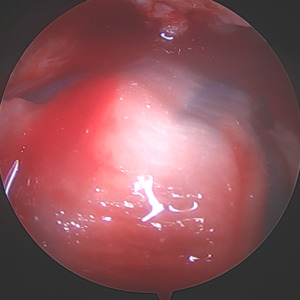

Due to the delaminated nature of the tear and active work as a laborer, biologic augmentation (TAPESTRY® Biointegrative Implant by Embody) was added to support tendon healing. This biologic augmentation was chosen due to the delamination and retraction of the rotator cuff as an increased change of retear is noted when present. The arthroscopic introducer was used from the lateral portal via the cannula. Once appropriately positioned over the delaminated area, three bioabsorbable anchors were used to fixate the implant in the tendon and bone, with two anchors placed medially in the soft tissue and two anchors placed laterally into bone.

I chose to include biologic augmentation due to the extensive delamination seen on the preoperative MRI as well as intraoperative findings. Several preoperative patient risk factors (age, BMI, smoking, diabetes) may be reviewed when considering biologic augmentation of a tear due to increased risk of retearing or poor healing. The bioaugmentation used is a highly aligned, porous collagen implant which supports formation of new tendon-like tissue. The alignment and significant porosity of the implant allows for increased cell proliferation and remodeling. The implant covers a wide surface area and can be precisely placed arthroscopically over the area of concern. Another benefit of the bioaugmentation implant is that it may increase tendon thickness during healing, which could allow for better post-operative results. Furthermore, using it to augment the tendon does not require any additional post-operative protocols outside of the standard protocol.

Unlike other collagen implant fixation, this system allows the implant to be fixated with bioabsorbable anchors which can be used in both tendon and bone. The dual anchor inserter does not require any bony prep work before inserting the anchors into bone, allowing for an efficient workflow. Additionally, the system includes the streamlined delivery of the pre-loaded implant to the arthroscopic space on the implant.